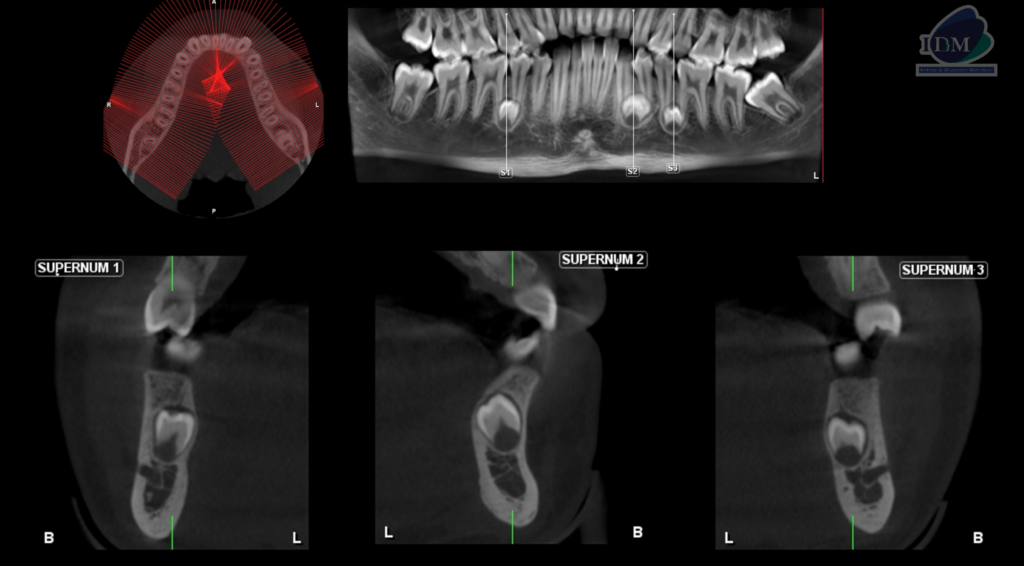

RECONSTRUCCIÓN 3D

Así mismo en la tomografía volumétrica de haz se evidencia:

- Supernumerario 1: retenida en posición vertical y en contacto con los segmentos radiculares de las piezas 45 y 46, a nivel apical y orientado hacia lingual.

- Supernumerario 2: retenida en posición vertical y en contacto con los segmentos radiculares de las piezas 33 y 34, a nivel apical y orientado hacia lingual.

- Supernumerario 3: retenida en posición vertical y en contacto con los segmentos radiculares de las piezas 35 y 36, a nivel apical y orientado hacia lingual.

Conclusión imagenológica:

- Presencia de tres dientes supernumerarios